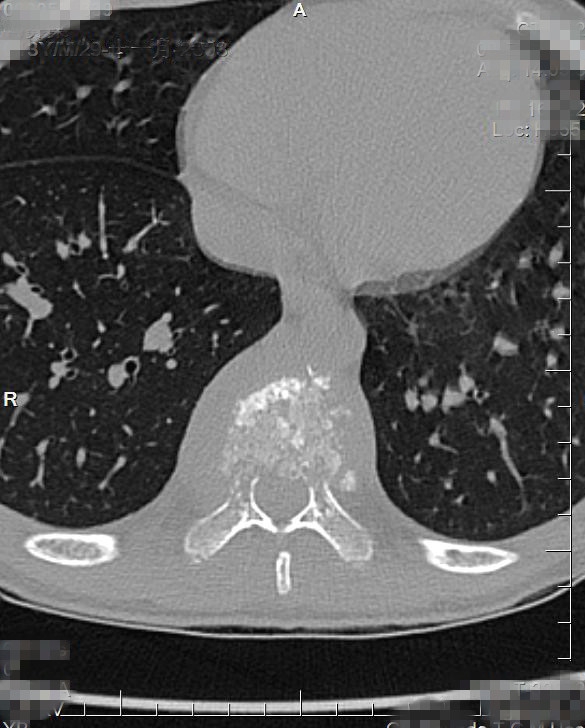

入院CT:结合MRI考虑,T9椎体病理性压缩性骨折,双侧椎弓根骨折,伴周围软组织感染性改变。

CT